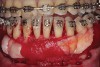

Fig 2. Full-thickness flap reflection. Note

dehiscence and fenestrations throughout. Orthodontic walls are limited to nonexistent.

Figure 2

Fig 3. Corticotomy cuts performed.

Figure 3